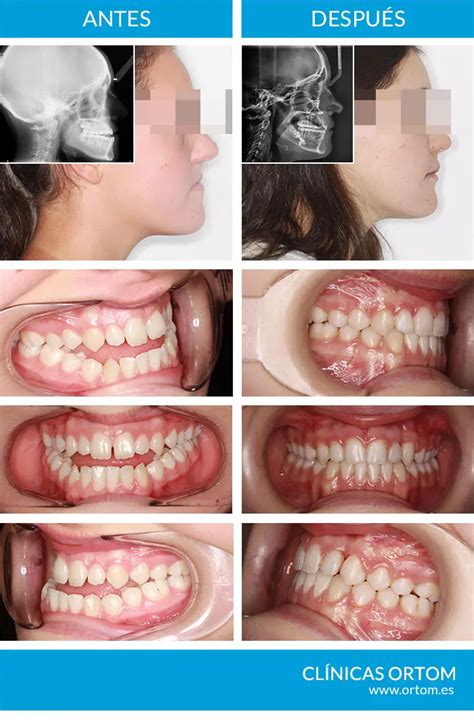

Este tipo de anomalías se corrigen mediante la cirugía ortognática, un procedimiento que se realiza bajo anestesia general. Es importante que esta intervención la realice un cirujano maxilofacial, aunque es posible que deba trabajar en conjunto con un especialista en ortodoncia. De esta forma se corregirá la posición de los huesos maxilares y a su vez la forma de la dentadura.

La cirugía consiste en realizar una serie de incisiones por la parte interna de la boca y reubicar los maxilares, aunque a veces es necesario cortar parte del hueso. Después, la mandíbula o maxilar es fijado en el lugar mediante tornillos. Este tipo de cirugía puede llegar a ser compleja y el tiempo de recuperación del paciente es de aproximadamente un mes, pero los resultados suelen ser muy satisfactorios.